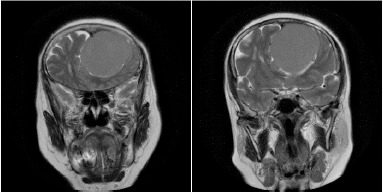

Case report: We present a case of a 59-year-old female with a history of progressive headache, anosmia, mental status changes, and progressive poor vision. Ocular examination revealed disc pallor in her left eye with disc oedema in the contralateral eye. The patient was sent for computerized tomography (CT) and MRI, and the diagnosis of frontal lobe meningioma was confirmed. The surgical removal was performed, and the condition improved gradually.